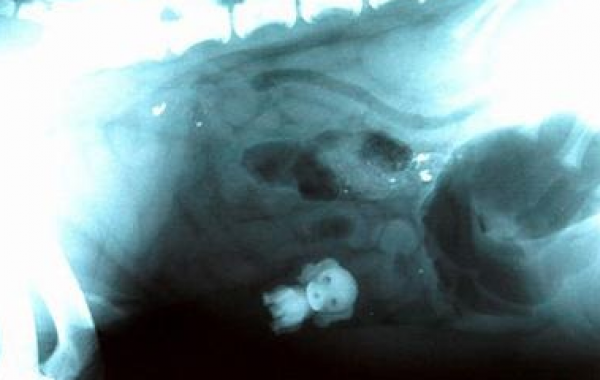

Рентгеновские снимки собак, внутри которых были найдены самые невероятные вещи рентген 20.09.2014 4212